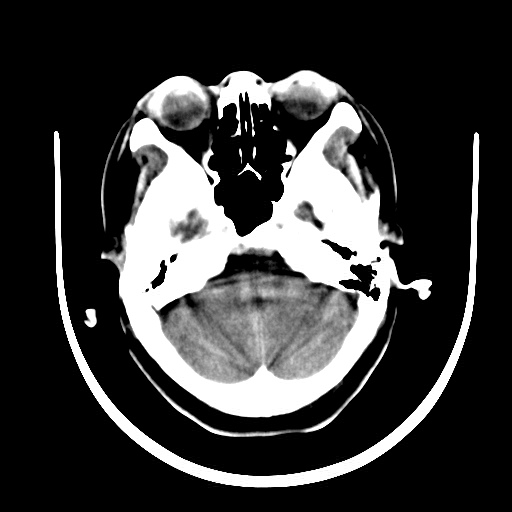

标题: CT16579:女 65岁间断性抽搐. [打印本页]

标题: CT16579:女 65岁间断性抽搐.

考虑右侧颞叶脑软化灶并脑穿通畸形;建议必要时行进一步检查。

右侧蛛网膜囊肿

右颞叶脑软化灶。余未见明显异常。

考虑右颞叶脑软化灶

右颞叶软化灶,右基底节区腔隙性脑梗塞;